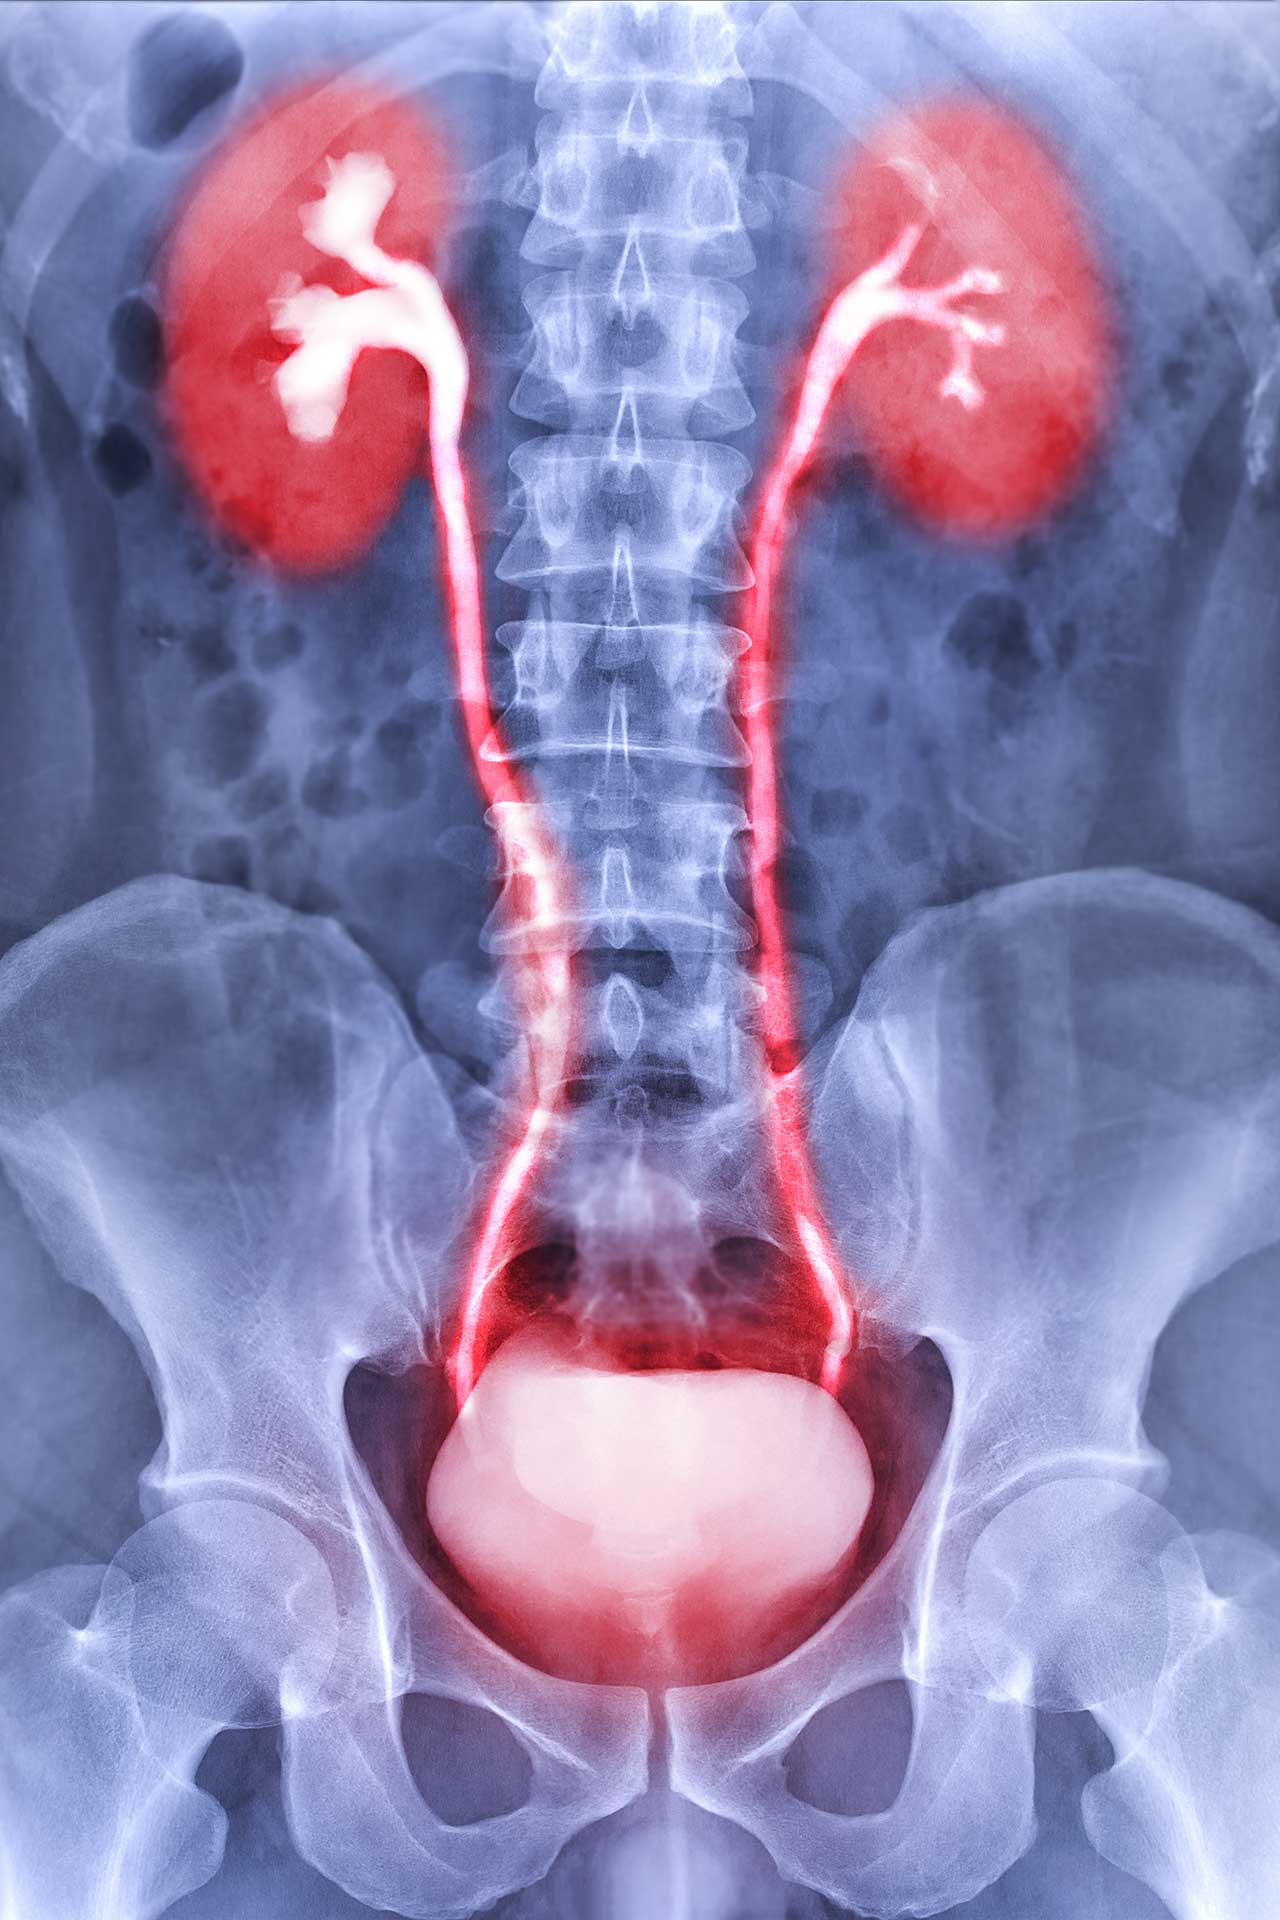

Durch Röntgenuntersuchungen in der Urologie kann entweder das gesamte ableitende Harnsystem oder ein spezieller Bereich untersucht werden. Die meisten urologischen Röntgenuntersuchungen werden mit Kontrastmittel durchgeführt.

- Infusionsurogramm

Diese Röntgenuntersuchung der Nieren, der Harnleiter und der Blase ermöglicht die Diagnostik von Tumoren des ableitenden Harnsystems, exakte Lokalisation und Darstellung von Steinen und Harnabflusstörungen. - Urethrogramm

Durch Einbringen eines Kontrastmittels in die Harnröhre wird diese auf mögliche Engstellen untersucht. - Miktions-Cysto-Urogramm (MCU)

Beim sog. MCU wird eine Röntgenuntersuchung der Harnblase beim Wasserlassen durchgeführt. Dies lässt einen Rückschluss darauf zu, ob ein Rückfluss des Urines in die Harnleiter oder sogar die Nieren besteht. Ein solcher Reflux kann zu wiederkehrenden Harnwegsinfekten und zu fieberhaftem Nierenbeckenentzündungen führen.